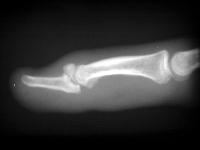

Clinical Example: Mallet fingers

mallet finger